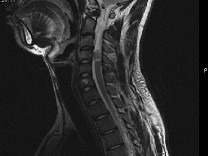

男,24岁,颈部疼痛,并右上肢麻木,以手部明显,请根据所提供图像,选择最可能的诊断()

A.(颈4~5)神经鞘瘤

B.(颈4~5)脊膜瘤

C.(颈4~5)海绵状血管瘤

D.(颈4~5)血管母细胞瘤

E.(颈4~5)胶质瘤

男,24岁,颈部疼痛,并右上肢麻木,以手部明显,请根据所提供图像,选择最可能的诊断()<img border="0" style="width: 225px; he

[单选题]男,24岁,颈部疼痛,并右上肢麻木,以手部明显,请根据所提供图像,选择最可能的诊断()A.(颈4~5)神经鞘瘤B.(颈4~5)脊膜瘤C.(颈4~5)海

男,24岁,颈部疼痛,并右上肢麻木,以手部明显,根据所提供图像,最可能的诊断是<img border="0" style="width: 301px; height

[单选题]男,24岁,颈部疼痛,并右上肢麻木,以手部明显,根据所提供图像,最可能的诊断是A.(颈4~5)神经鞘瘤B.(颈4~5)脊膜瘤C.(颈4~5)海绵状血管

男,24岁,颈部疼痛,并右上肢麻木,以手部明显,根据所提供图像,最可能的诊断是<img border="0" style="width: 301px; height

[单选题]男,24岁,颈部疼痛,并右上肢麻木,以手部明显,根据所提供图像,最可能的诊断是A.(颈4~5)神经鞘瘤B.(颈4~5)脊膜瘤C.(颈4~5)海绵状血管

男,24岁,颈部疼痛,并右上肢麻木,以手部明显,请根据所提供图像,选择最可能的诊

[单选题]男,24岁,颈部疼痛,并右上肢麻木,以手部明显,请根据所提供图像,选择最可能的诊断()A . 颈4~5)神经鞘瘤B . 颈4~5)脊膜瘤C . 颈4~5)海绵状血管瘤D . 颈4~5)血管母细胞瘤E . 颈4~5)胶质瘤

男,24岁,颈部疼痛,并右上肢麻木,以手部明显,根据所提供图像,最可能的诊断是(

[单选题]男,24岁,颈部疼痛,并右上肢麻木,以手部明显,根据所提供图像,最可能的诊断是()A . (颈4~5)神经鞘瘤B . (颈4~5)脊膜瘤C . (颈4~5)海绵状血管瘤D . (颈4~5)血管母细胞瘤E . (颈4~5)胶质瘤